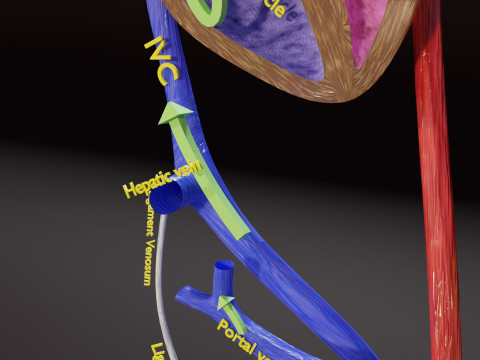

The model meshes include adult circulation versus circulation in Tetralogy of Fallot (TAF), arrow labels and text labels. The blood flow in a patient with Tetralogy of Fallot is outlined in this model. To contrast it to normal blood circulation a separate model of normal circulation is included. The Tetralogy of Fallot (OVER RIDING OF AORTA, PUL STENOSIS, VENTRICULAR SEPTAL DEFECT, RIGHT VENTRICULAR HYPERTROPHY), fossa, ligament teres , venosus, and arteriosus are duly depicted with proper labelling and blood flow directional arrows. Excellent model for teaching, demonstration and knowlegde of human body. The models include both procedural and image textures blend files separately. The texture file include diffuse, roughness and normal png and jpeg based on non overlapping UV maps.